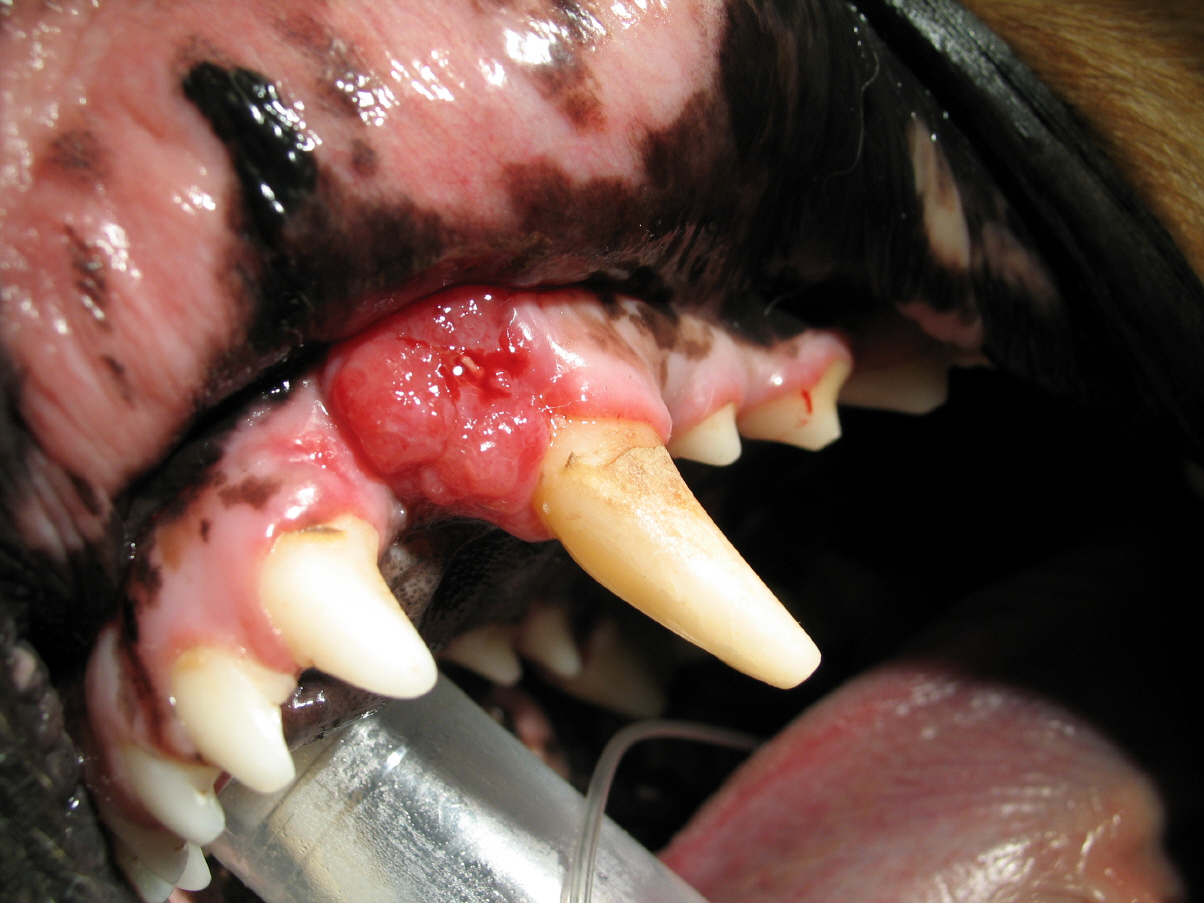

Operation

Aufgrund des Einwachsens des Tumores in den Knochen musste bei Max ein Teil des Oberkiefers und 3 Zähne entfernt werden. Max konnte noch am selben Tag entlassen werden. Er erhielt über einige Tage ein Schmerzmittel. Bereits am Tag nach der Operation hatte Max schon wieder einen guten Appetit.